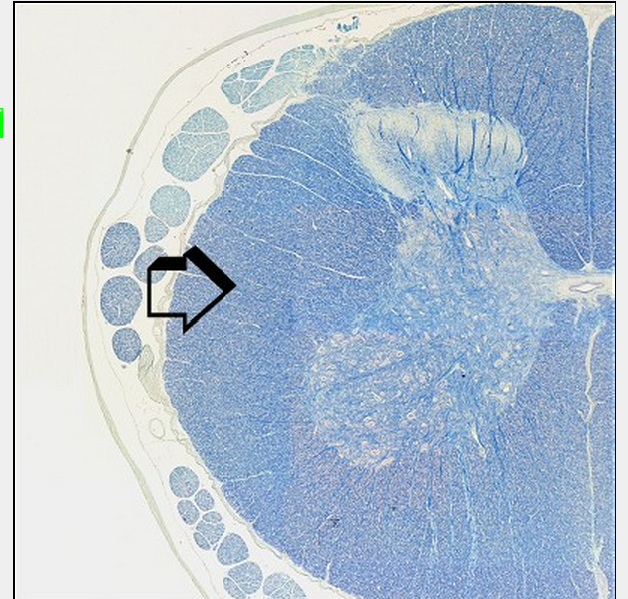

Which matter of the brain is the arrow indicating? What part of the brain is this then?

A

Grey Matter

The grey matter is central in the spinal cord